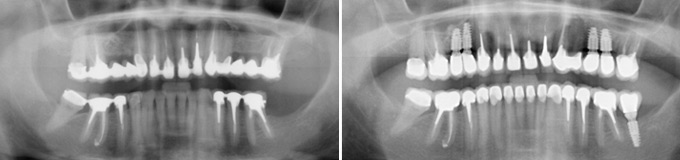

Je veux retrouver l’ensemble de mes dents individuelles comme «au naturel».

Solution : autant de couronnes fixes sur implants que de dents manquantes.

Je veux supprimer les bridges et retrouver un beau sourire.

Au final toutes les dents sont individualisées et les manquantes remplacées par des implants.